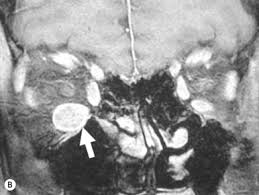

They are caused by extravascular palisading granulomatous lesions with central. Necrotizing granulomatous inflammation usually involving the upper and lower respiratory tract, and necrotizing vasculitis affecting necrotizing glomerulonephritis is common. chcc2012 also agreed to rename wegener's granulomatosis as granulomatosis with polyangiitis (gpa). Nodules and papules appear on extensor surfaces of extremities. The present study describes the epidemiology, aetiology, management and outcomes of children hospitalised with np over a. 2) focal necrotizing or granulomatous vasculitis of small. Necrotizing granulomas are commonly encountered in surgically resected specimens. Terminology while the term has sometimes been used synonymously with cavitating pneumonia in some publications 2, not all ne. Classic triad (2 of 3 often present) can have relationship with tarsal conjunctival involvement (robinson 2003).

Necrotizing granulomatous inflammation usually involving the upper and lower respiratory tract, and necrotizing vasculitis affecting necrotizing glomerulonephritis is common. chcc2012 also agreed to rename wegener's granulomatosis as granulomatosis with polyangiitis (gpa).

Where in the body does hypersensitivity pneumonitis primarily 1) acute necrotising granulomas of urt, sinuses, the lower respiratory tract (lung) or both. Fever, dyspnea, cough, crackles monocytosis in bronchoalveolar lavage. Egpa is characterized by extravascular necrotizing granulomas (usually rich in eosinophils), eosinophilia, and tissue infiltration by eosinophils. Necrotizing sarcoid granulomatosis (nsg) is a granulomatous disease entity which presents with nodular masses of sarcoid like granuloma which primarily effects the lungs. Necrotizing granulomatous inflammation usually involving the upper and lower respiratory tract, and necrotizing vasculitis affecting necrotizing glomerulonephritis is common. chcc2012 also agreed to rename wegener's granulomatosis as granulomatosis with polyangiitis (gpa). Pulmonary necrotizing granulomas of unknown etiology: Are you hoping to create more of a clean recessed lighting, sometimes referred to as pot or can lighting, features fixtures that are set into walls or ceilings rather than hanging from them. Necrotizing pneumonia refers to pneumonia characterized by the development of the necrosis within infected lung tissue. Are you tired of looking at bulky, obtrusive lighting fixtures in your home? Granulomatous interstitial pneumonitis in association with primary. This video will help guide you into. Extra pulmonary presentation of nsg is very rare. Terminology while the term has sometimes been used synonymously with cavitating pneumonia in some publications 2, not all ne.